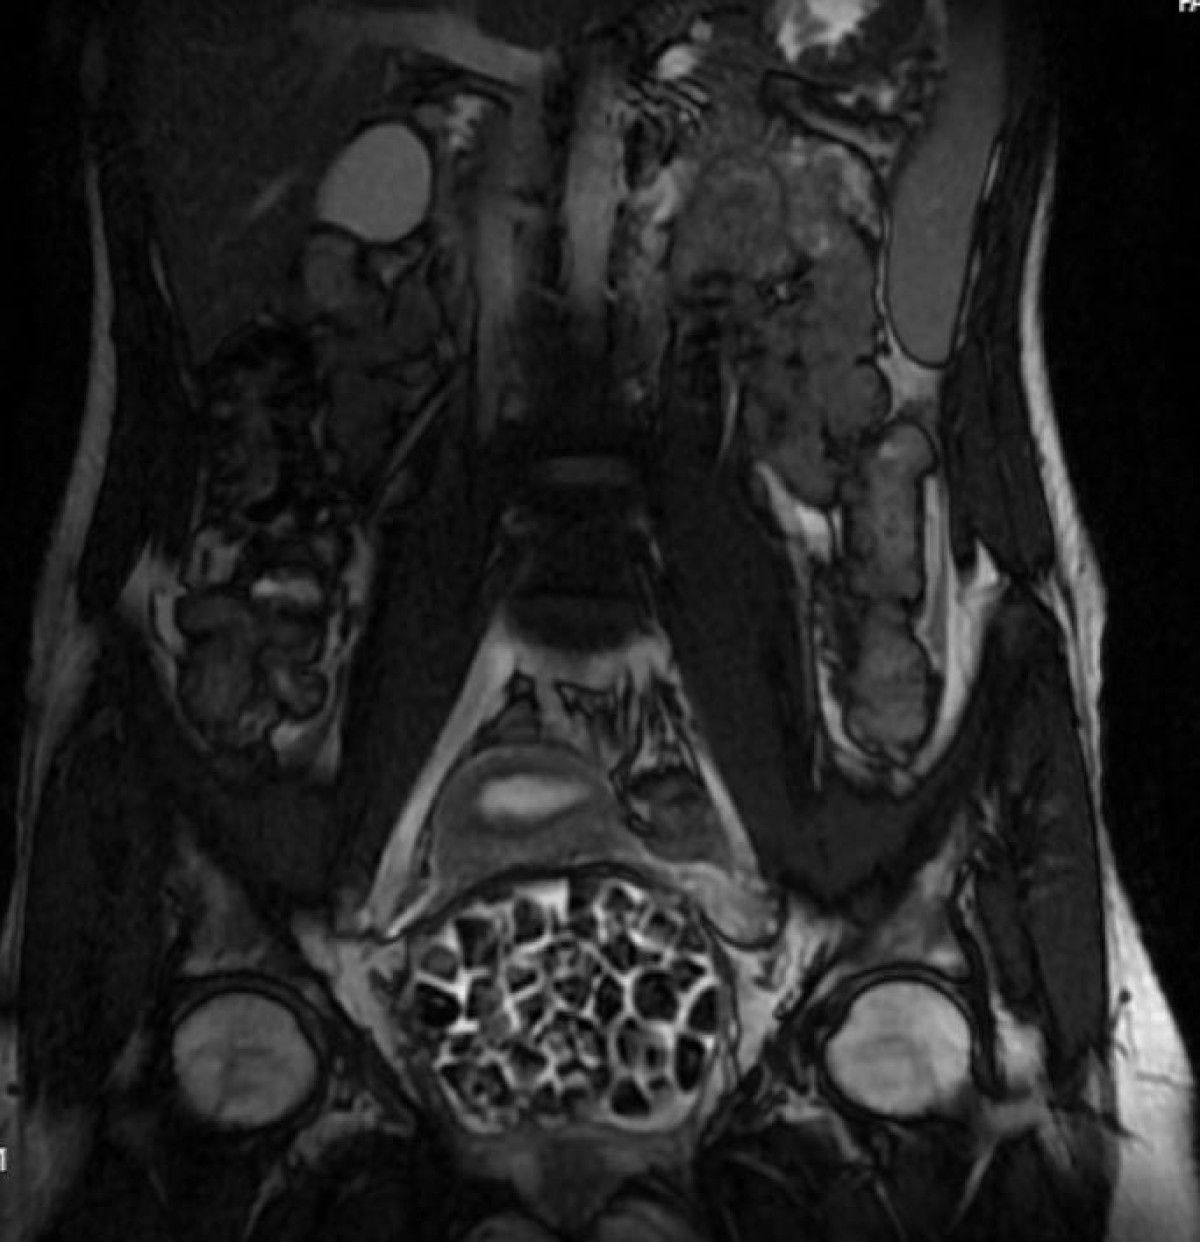

Öztürk’ün bedeninden 287 adet çeşitli ölçülerde taş çıkarılırken üroloji ve jinekolojik onkoloji grubu operasyonu muvaffakiyetle tamamladı. Taşların sayısını duyan genç kız ve ailesi şoke olurken operasyonun akabinde karın ağrıları dinen Öztürk, rahat bir nefes aldı. Tedavisi sonrası taburcu edilen genç kız yaşadıklarını anlatırken, operasyonu gerçekleştiren Üroloji Uzmanı Doç. Dr. Erkan Erkan ile Jinekolojik Onkoloji Uzmanı Op. Dr. Emin Erhan Dönmez de ender olduğunu söz ettikleri olayları hakkında bilgi verdi, kıymetli ikazlarda bulundu. Öte yandan, genç kızın bedenindeki 287 taşın tetkiklerdeki imajı dikkat çekerken taşlar üzerine de incelemeler yapılacak.

Hastasının durumuna yönelik konuşan Üroloji Uzmanı Doç. Dr. Erkan Erkan, “Hastamızın 2004 yılında doğduğunu akabinde doğar doğmaz ekstrofi vezika dediğimiz 50 binde bir görülen bir anomaliden ötürü arka arda ameliyatlar geçirdiğini öğrendik. 10 yaşında yeniden bir ameliyat geçirmişti, gerekli görüntüleme ve tetkiklerimizi yaptırdık. Olağanda mesanesinin olması gereken yerin çabucak art kısmında taşlarla dolu bir kese olduğunu gördük, bunun üzerine ek görüntülemeler; MR çektirdik. Hastamız çelişkili açıklamalar almıştı, kendi radyolojik kliniğimiz ve edindiğimiz konsültasyonlarda taşların mesanede değil vajinal boşlukta oluştuğunu düşündük, bir planlama yaptık.

Genç kızın uzun müddettir devam eden karın ağrısı olduğunu söyleyerek kelamlarına başlayan Jinekolojik Onkoloji Uzmanı Op. Dr. Emin Erhan Dönmez, “Mesane taşları olduğu düşünülerek daha büyük bir hastaneye refere edilmiş. Ortamızda küçük bir kurul yaparak muayene ettik. Vajen bir hazne misyonu görerek orada durağan bir idrar, uzun mühlet beklediği için idrar içindeki minerallerde çökerek taşlar oluşmuş. Mesanedeki idrarın vajene akmış olabileceği ve vajende göllenen idrar nedeniyle taşların burada oluşacağını düşündük, ameliyatımızı planladık. Ameliyata teşhis hedefli girmiştik, sistoskopi (Mesane üzere idrar yollarını kapsayan kısımlardaki rahatsızlıkların teşhis ve tedavisinde kullanılan endoskopik bir yöntem) dediğimiz ameliyatı Erkan Hocam ile birlikte gerçekleştirdik.

Önce mesaneyi bir görüntüledik, mesane tabanına yaklaşık 2-3 cm’lik bir alandan vajene fistülize olduğunu gördük. Mesaneden vajene geçtiğimiz esnada tüm vajenin taşlarla dolu olduğunu gördük. Teşhis hedefiyle girdiğimiz ameliyatta her şey de olağan gittiği için tedaviye geçtik. Taşların çıkabileceği kadar bir genişlik sağladık. Daha sonra yaklaşık en büyüğü 2,5 cm boyutlarında olan, irili ufaklı 287 tane taşı ameliyat esnasında çıkarmış olduk. Taşların tekrarlamaması için idrarın göllenmemesi, en azından dışarıya rahatça boşalabilmesi için vajinal rekonstrüksiyonu sağladık. Ameliyatta da rastgele bir sorun yaşamadık. Literatürü Erkan Hocam ile birlikte değerlendirmiştik. Primer olarak vajende birikmiş olan bu kadar çok sayıda taşla ilgili bir makale görmedik, rastlamadık.” dedi.